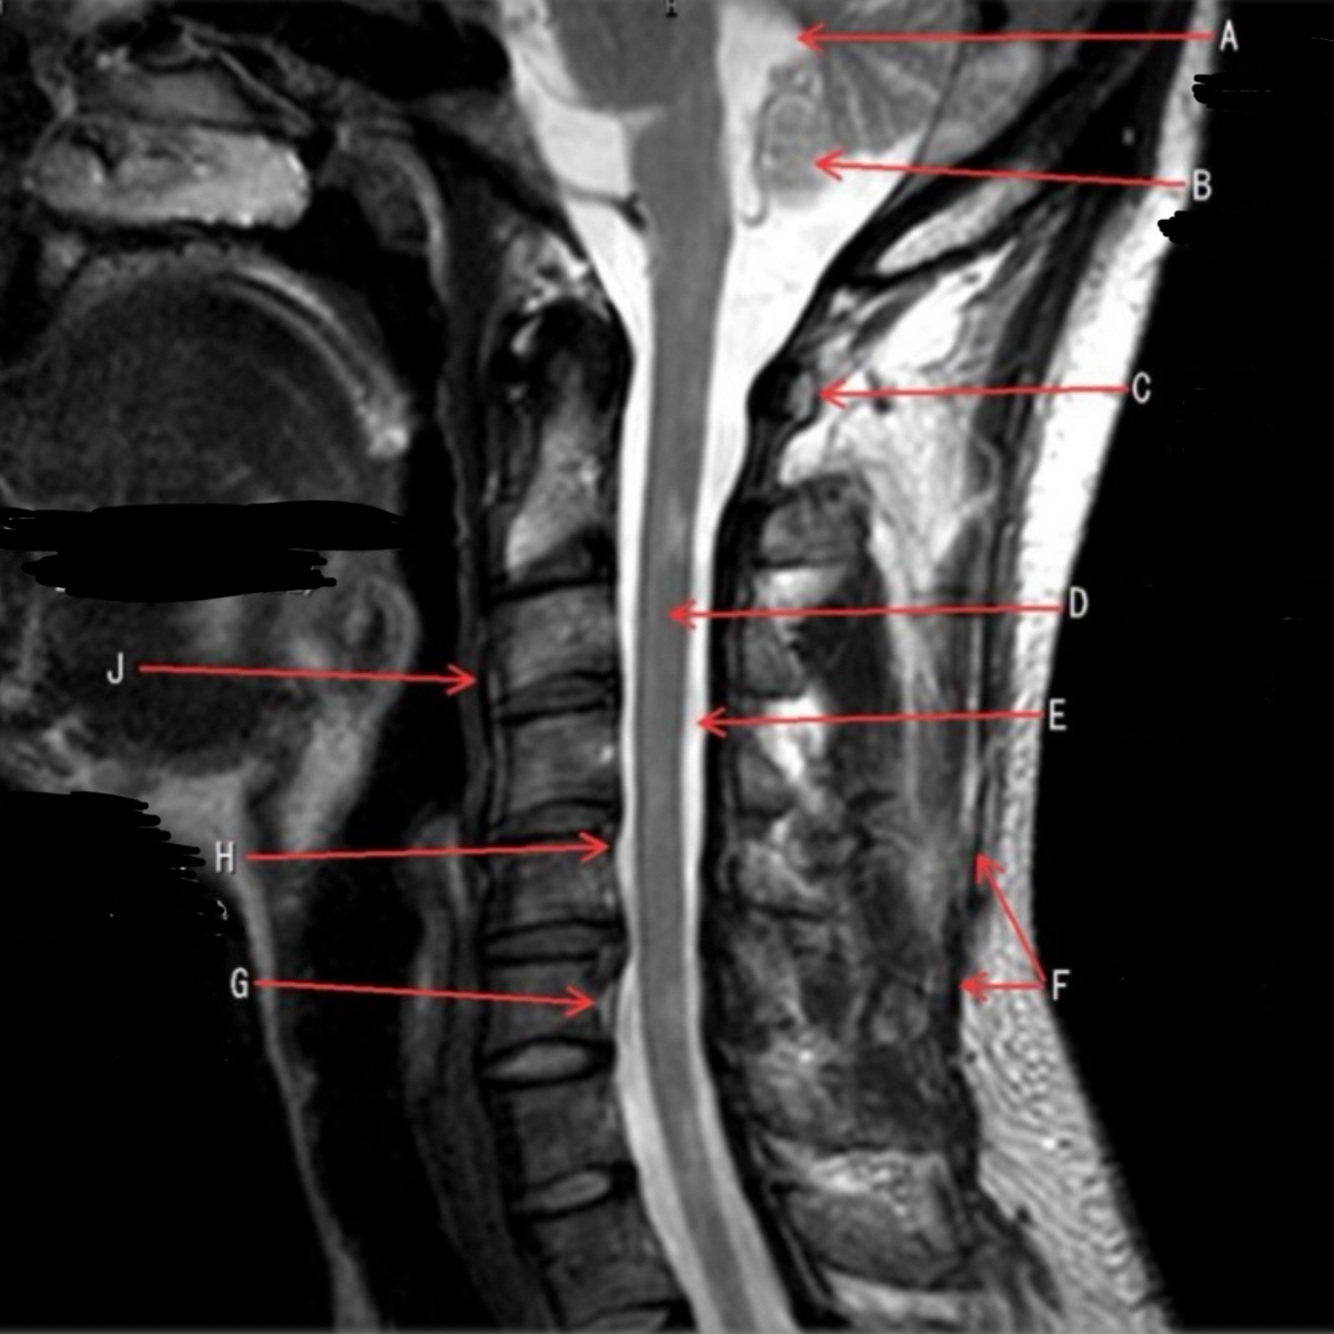

10

What is letter A?

CSF

11

What is letter B?

SPINAL CORD

12

What is letter C?

LAMINA

13

What is letter D?

DORSAL NERVE ROOT

14

What is letter E?

VENTRAL NERVE ROOT

15

What is letter F?

VERTEBRAL BODY

16

What is letter G?

SPINOUS PROCESS

17

What is letter H?

TRANSVERSE PROCESS

18

What is letter J?

VERTEBRAL ARTERY